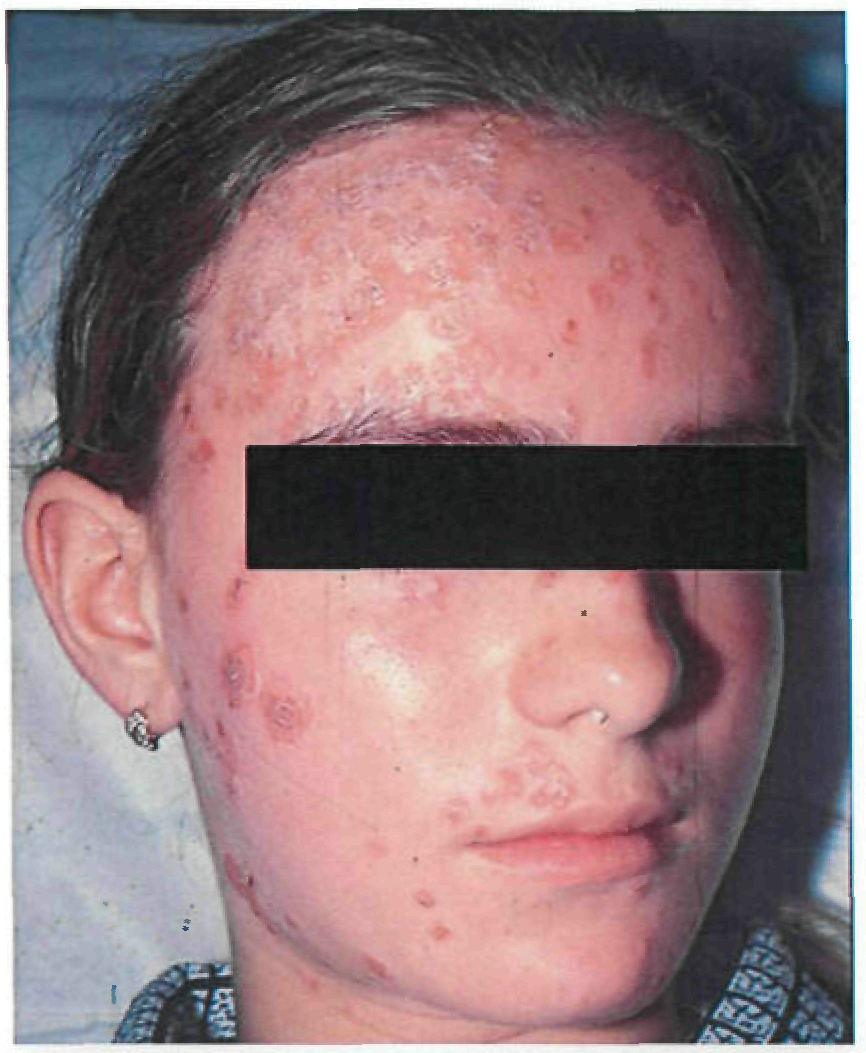

Период высыпаний

На 3-4-й день болезни температура тела снижается до субфебрильной, одновременно на коже головы (прежде всего на лице) и на слизистых оболочках полости рта, гениталий, конъюнктивы, роговицы глаз появляются необильные элементы сыпи. Энантема на слизистых оболочках полости рта обычно предшествует появлению экзантемы. Первые элементы сыпи обычно появляются на лице, быстро распространяясь на верхние конечности, а затем - на туловище и нижние конечности, поражая ладони и подошвы. Распространение экзантемы имеет центробежный характер - на туловище элементов меньше, чем на лице и конечностях.

В 95% случаев сыпь поражает лицо, в 75% - ладони и подошвы, что является отличительным признаком заболевания. Также поражаются слизистые оболочки полости рта (в 70% случаев), половые органы (30%), конъюнктива и/или роговица (20%). У части пациентов имеет место проктит с поражениями перианальной области изолированно или в сочетании с высыпаниями в области гениталий [39]. Количество элементов сыпи варьирует от единичных до нескольких тысяч [13].

Согласно данным ВОЗ у многих пациентов с МРХ, выявленных в 2022 г. в неэндемичных по данному заболеванию странах, заболевание протекает в атипичной форме, включающей следующие признаки: появление небольшого количества элементов сыпи или только одного элемента, которые возникают в области гениталий или промежности и не распространяются на другие участки кожи; наличие очагов поражения кожи на разных (асинхронных) стадиях развития; появление сыпи до начала увеличения лимфатических узлов, лихорадки, недомогания или других симптомов [41].

Осложнения оспы обезьян связаны преимущественно с присоединением вторичной бактериальной инфекции: абсцессы, флегмоны, бронхопневмония, кератит (с возможной потерей зрения), гастроэнтерит с диареей и рвотой, энцефалит, сепсис, септический шок. Развитие неблагоприятных исходов и осложнений МРХ наблюдается реже среди пациентов, вакцинированных против натуральной оспы [28].